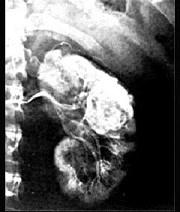

问题 肾皮质多发性脓肿区别于肾癌的是前者 ( )

选项 A、尿中未查到癌细胞 B、没有血尿 C、患者发热、腰痛,经皮肾穿刺抽吸出脓液 D、排泄性尿路造影肾盏受压变形 E、B超、CT检查肾实质有占位性病变

答案 C